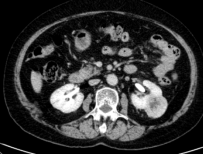

廣泛開展腹腔鏡下腎癌根治術(shù)、腎盂癌根治術(shù)、腎部分切除術(shù)、腎腫瘤剜除術(shù)、腎上腺腫瘤切除術(shù)、腎盂輸尿管成形術(shù)、腎囊腫去頂減壓術(shù)、輸尿管上段切開取石術(shù)等。全腔鏡下進(jìn)行,創(chuàng)傷小、恢復(fù)快。

腹腔鏡腎腫瘤剜除術(shù)(保腎) 腹腔鏡腎癌根治術(shù) 腹腔鏡腎盂癌根治術(shù)